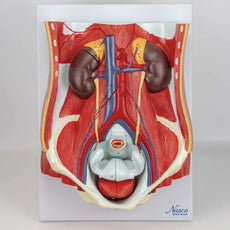

This Urinary System all-in-one-model shows:- Structures of retroperitoneal cavity

- Large and small pelvis with bones and muscles

- Inferior vena cava

- Aorta with its branches including iliacal vessels

- Upper urinary tract

- Rectum

- Kidney with adrenal gland.

One front half of a kidney is removable from the anatomical model of the urinary system. With easy to change male insert (bladder and prostate, front and rear half) and female insert (bladder, womb and ovaries, 2 lateral halves) the Urinary System model is a great teaching tool.

Dual Sex Urinary System model on baseboard.